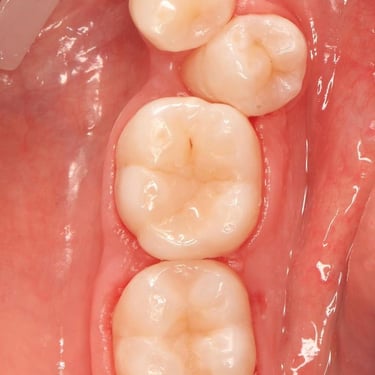

COMPOSITE FILLINGS

Dental fillings are materials used to repair cavities and restore damaged teeth, preventing further decay and restoring tooth function and shape.